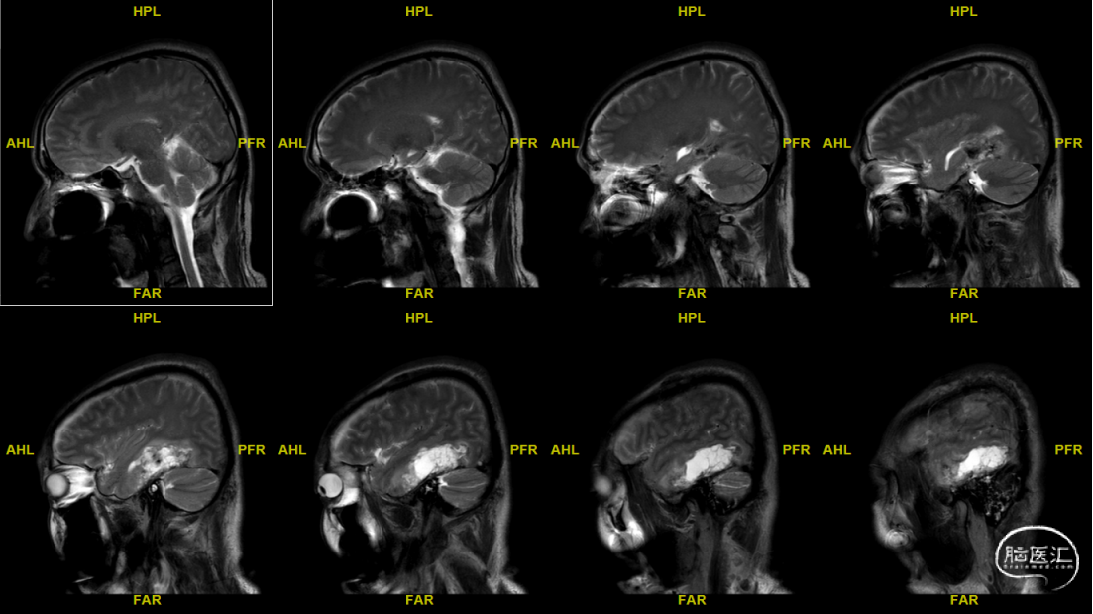

术前MRI

DTI-视辐射

术后MRI